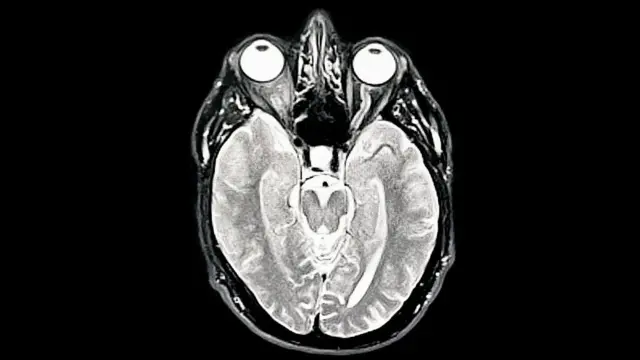

El cerebro pasa por cinco fases distintas en la vida, con puntos de inflexión clave a los 9, 32, 66 y 83 años, afirma un grupo de científicos.

Los hallazgos forman parte de un estudio en el que participaron alrededor de 4.000 personas de hasta 90 años, quienes se sometieron a escáneres que mostraron las conexiones entre sus neuronas.

Investigadores de la Universidad de Cambridge , en Inglaterra, demostraron que el cerebro permanece en la fase adolescente hasta los 30 años, cuando alcanzamos nuestro máximo potencial.

Afirman que los resultados podrían ayudarnos a comprender por qué el riesgo de sufrir trastornos de salud mental y demencia varía a lo largo de la vida.

El cerebro cambia constantemente en respuesta a nuevos conocimientos y experiencias, pero la investigación demuestra que no se trata de un patrón uniforme desde el nacimiento hasta la muerte.